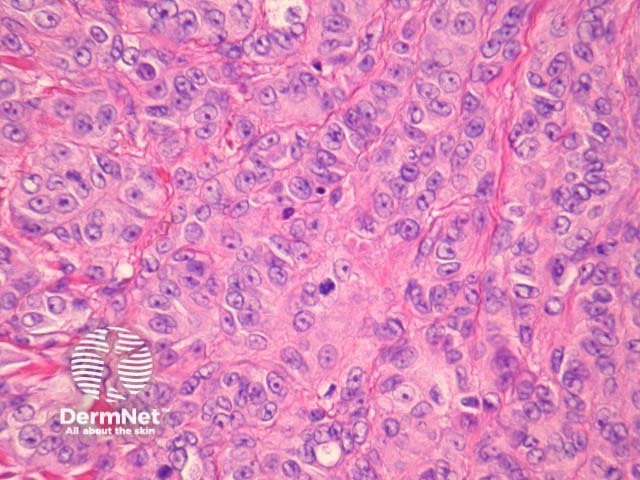

Nodular melanoma (NM) presents as a rapidly enlarging nodule. Histologically there is a dermal mass of dysplastic tumour cells with upward epidermal invasion but minimal adjacent epidermal spread or horizontal growth. Tumour cells are often round and epithelioid in morphology with hyperchromatic nuclei. See Figure 16, 17.

Figure 16

Figure 17